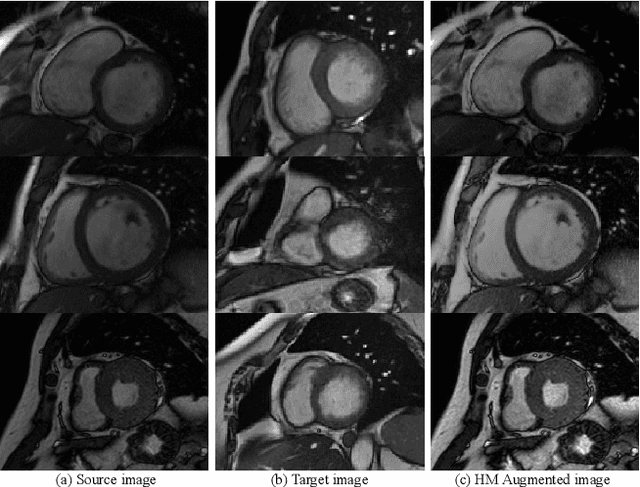

Convolutional Neural Networks (CNNs) have achieved high accuracy for cardiac structure segmentation if training cases and testing cases are from the same distribution. However, the performance would be degraded if the testing cases are from a distinct domain (e.g., new MRI scanners, clinical centers). In this paper, we propose a histogram matching (HM) data augmentation method to eliminate the domain gap. Specifically, our method generates new training cases by using HM to transfer the intensity distribution of testing cases to existing training cases. The proposed method is quite simple and can be used in a plug-and-play way in many segmentation tasks. The method is evaluated on MICCAI 2020 M\&Ms challenge, and achieves average Dice scores of 0.9051, 0.8405, and 0.8749, and Hausdorff Distances of 9.996, 12.49, and 12.68 for the left ventricular, myocardium, and right ventricular, respectively. Our results rank the third place in MICCAI 2020 M\&Ms challenge. The code and trained models are publicly available at \url{https://github.com/JunMa11/HM_DataAug}.